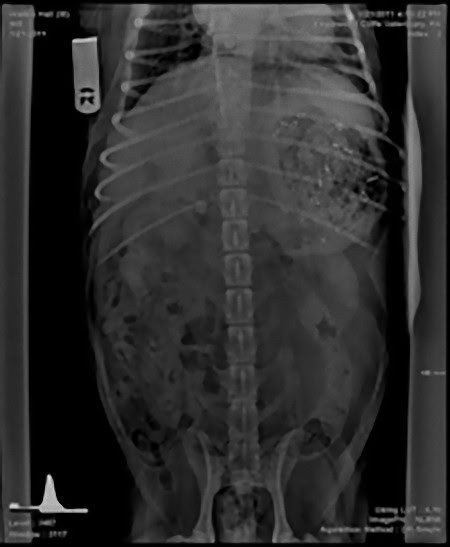

この画像を大きなサイズで見る4歳のラブラドール スプーン

この画像を大きなサイズで見る